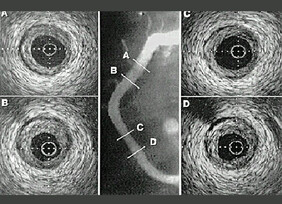

Intra Vascular Ultrasound (IVUS)

Optical Coherence Tomography (OCT)

This is similar to IVUS but uses light instead of ultrasound to achieve its images. it is a new technique which is being increasingly used as its pictures are far more detailed than those achieved with IVUS. As with IVUS it provides information regarding shape and size of arteries but also amount and type of fat build up.